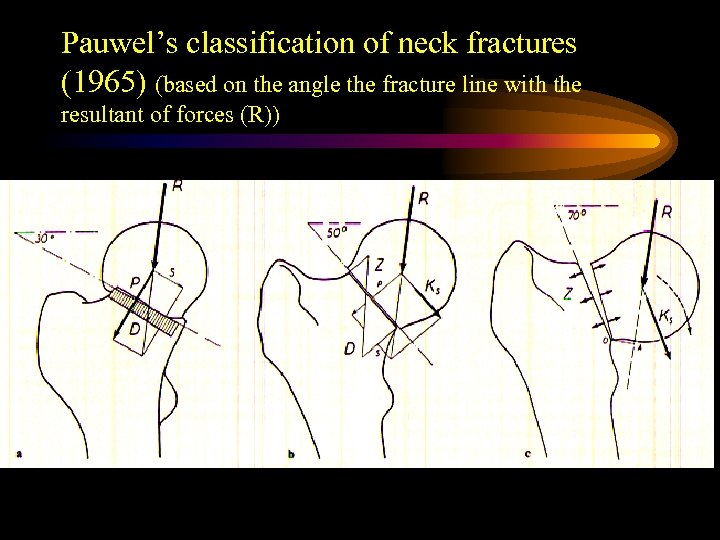

Pauwel’s classification of neck fractures (1965) (based on the angle the fracture line with the resultant of forces (R))

Pauwel’s classification of neck fractures (1965) (based on the angle the fracture line with the resultant of forces (R))